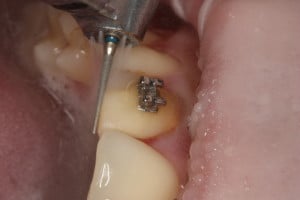

Przykład ekstruzji ortodontycznej za pomocą płytki termoformowalnej i zameczka ortodontycznego: